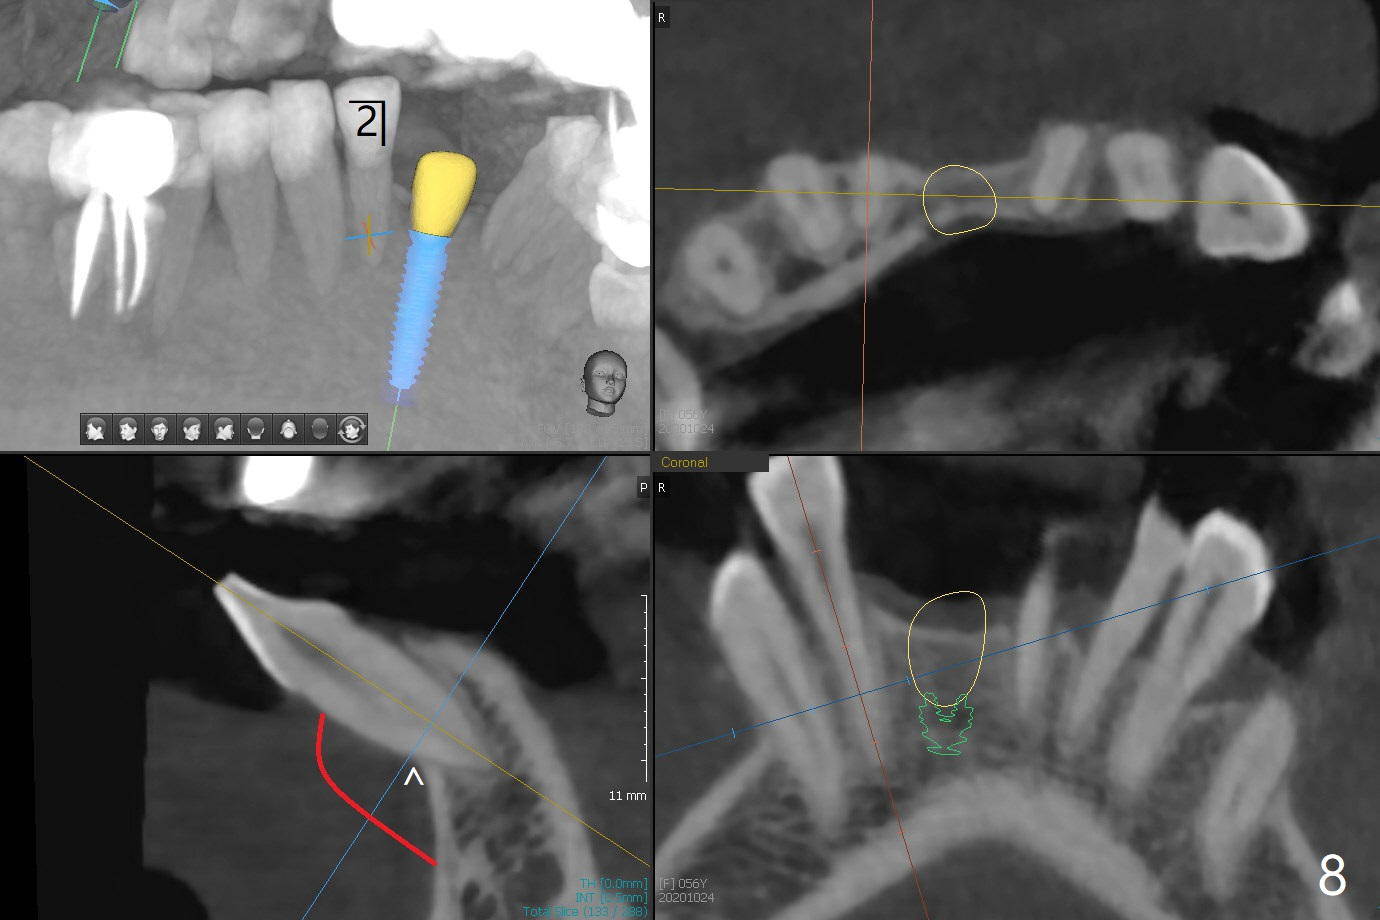

56岁女牙周炎,失去右上6,7以及右下1,后者缺牙间隙特别宽,其余切牙往颊侧移位(flare,病人不愿意拔除,图一)。右上植牙修复后(图二,三),下前牙种植(图四,五(选择窄植体)),建立正常覆盖,同时在邻近切牙唇侧植骨(图七,八:红线)。四-六个月后做局部矫正:使用植牙作为支抗将颊侧移位的前牙(牙冠)往舌侧推移(图七,八:蓝箭头),而牙根可能往唇侧移位(图六:红箭头),所以事先植骨(图七,八:红线)重要。矫正后3-3舌侧放置钢丝树脂固定。Jennifer: #25 implant and crown should be lingualized, as compared to the rest of the lower incisors (flared). After osteointegration, ortho will be conducted to correct the flaring using #25 implant as an anchor.